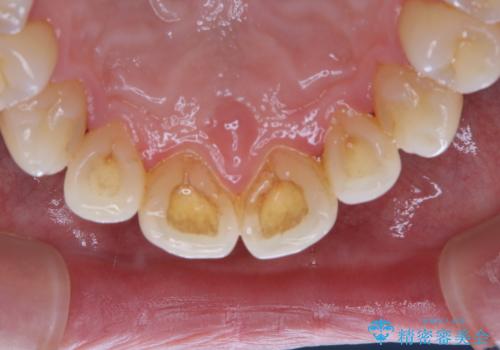

- 40年ほど歯科医院へ行ってなく、ザラつきがきになるとの事で来院されました。最近は普段の歯磨きの際、出血することがあり、歯ブラシ指導も希望されました。

お口全体に、歯垢・歯石が付着していたため、自費クリーニング(PMTC)60分コースを行い、徹底的に除去しました。

開始前

40年ぶりの来院との事で全体的に、古くからの歯垢・歯石が硬く多く付着していたため、自費クリーニング(PMTC)60分1万円+TAXコースを行いました。

日々の磨き残しなどをそのまま放置すると、細菌が固まり硬い歯石になります。

歯石になってしまうと、とても硬く、歯ブラシで取り除くことが出来なくなります。